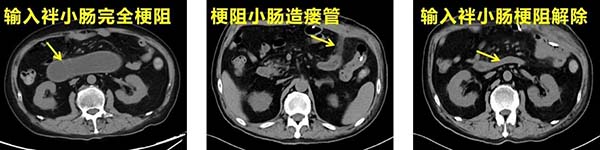

面对挑战,渠浩带领医疗团队制定了缜密的阶梯式治疗方案。首先,请介入医学科协助尝试放置输入袢小肠减压管来解除梗阻,但造影发现肿瘤已将输入袢小肠的开口完全堵塞,导丝无法通过;随即团队果断调整治疗策略,次日紧急实施腹腔镜下输入袢小肠造瘘术,术后患者腹胀症状即明显缓解,造瘘管引出大量墨绿色消化液;为避免患者消化液丢失,团队通过介入下空肠营养管建立消化液回输与肠内营养通路,为患者赢得关键的术前营养支持和体能恢复期。经过两周的系统营养支持与综合调理,患者身体状况显著改善,各项指标符合手术要求,迎来了肿瘤根治性手术的最佳时机。

腹腔镜小肠造瘘手术完全解除消化道梗阻